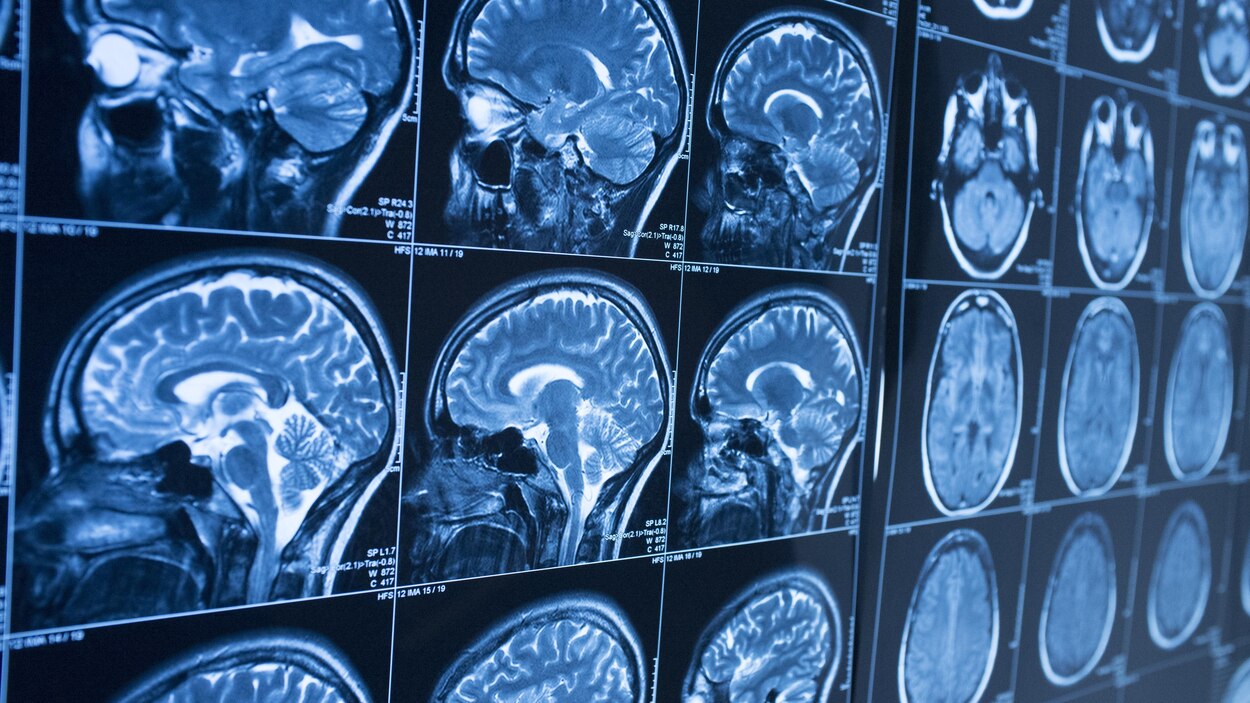

Scanner cerveau. Scanner m du cerveau liver scan échographie f du foie American English Would you like to translate a full sentence?. During the scan you will lie on a platform which slides into the scanner (a bit like going into a tunnel) It is important to lie still during the scan so that the machine can take clear pictures of your brain An MRI scan is usually a series of short scans with breaks in between, rather than one long scan. Le scanner permet par exemple de suivre l'évolution d'une hémorragie, d'une tumeur L’IRM mieux voir les organes, notamment le cerveau L' IRM (imagerie à résonance magnétique).

During the scan you will lie on a platform which slides into the scanner (a bit like going into a tunnel) It is important to lie still during the scan so that the machine can take clear pictures of your brain An MRI scan is usually a series of short scans with breaks in between, rather than one long scan. BOSTON(BUSINESS WIRE)May 4, Cerveau Technologies Inc today announced a research collaboration with University College London (UCL), a leading UK academic center for the production and application of imaging biomarkers for use in clinical research, that grants the institution the right to manufacture 18 FMK6240, a next generation investigational Positron Emission Tomography (PET. Scan (skăn) v scanned, scan·ning, scans vtr 1 a To look at carefully or thoroughly, especially in search of something;.

During the scan you will lie on a platform which slides into the scanner (a bit like going into a tunnel) It is important to lie still during the scan so that the machine can take clear pictures of your brain An MRI scan is usually a series of short scans with breaks in between, rather than one long scan. Neuromarketing scanner le cerveau un reportage de Canal Jimmy Genaro Jace Follow 6 years ago 47 views Neuromarketing scanner le cerveau un reportage de Canal Jimmy Report Browse more videos Playing next Cash investigation Neuromarketing votre cerveau les intéresse / intégrale. Et pour le coup je crois que si l'on scannait le cerveau de notre docteur en herbe, on y découvrirait de vastes zones de bêtise à l'état pur et très inquiétante pour notre système.

Le scanner a également révélé que le volume des zones ischémiques était supérieur de 47 % à l'échelle du cerveau chez ces mêmes sujets par rapport au reste de la population étudiée, et. Pour un scanner cérébral, le patient est allongé, en général sur le dos, sur un lit qui se déplace automatiquement dans un large anneau Il doit garder les deux bras sont allongés le long du corps et sa tête est immobilisée par une fixation dédiée. In addition to ultrasounds, another scan commonly used in standard cancer diagnosis is a CT scan CT stands for Computed Tomography It's an imaging tool that uses Xray technology to produce scans of the inside of the body.